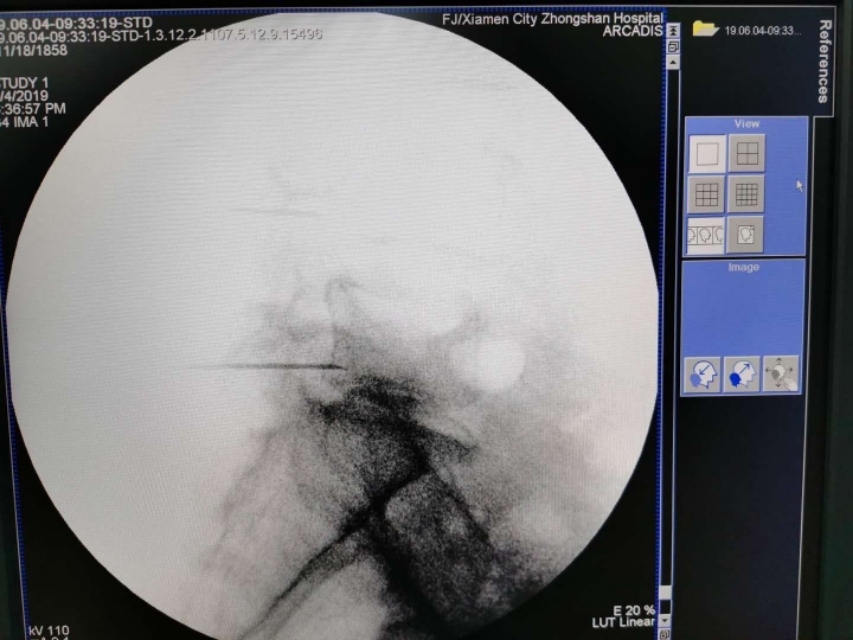

C臂透视左侧斜位片。腰4、腰5骶1左侧附件成苏格兰犬状。确定进针点。

在C臂辅助下穿刺针顺利到达目标靶点safety triangle

询问患者下肢没有异常。回抽证实处于安全区。遂注入药物。